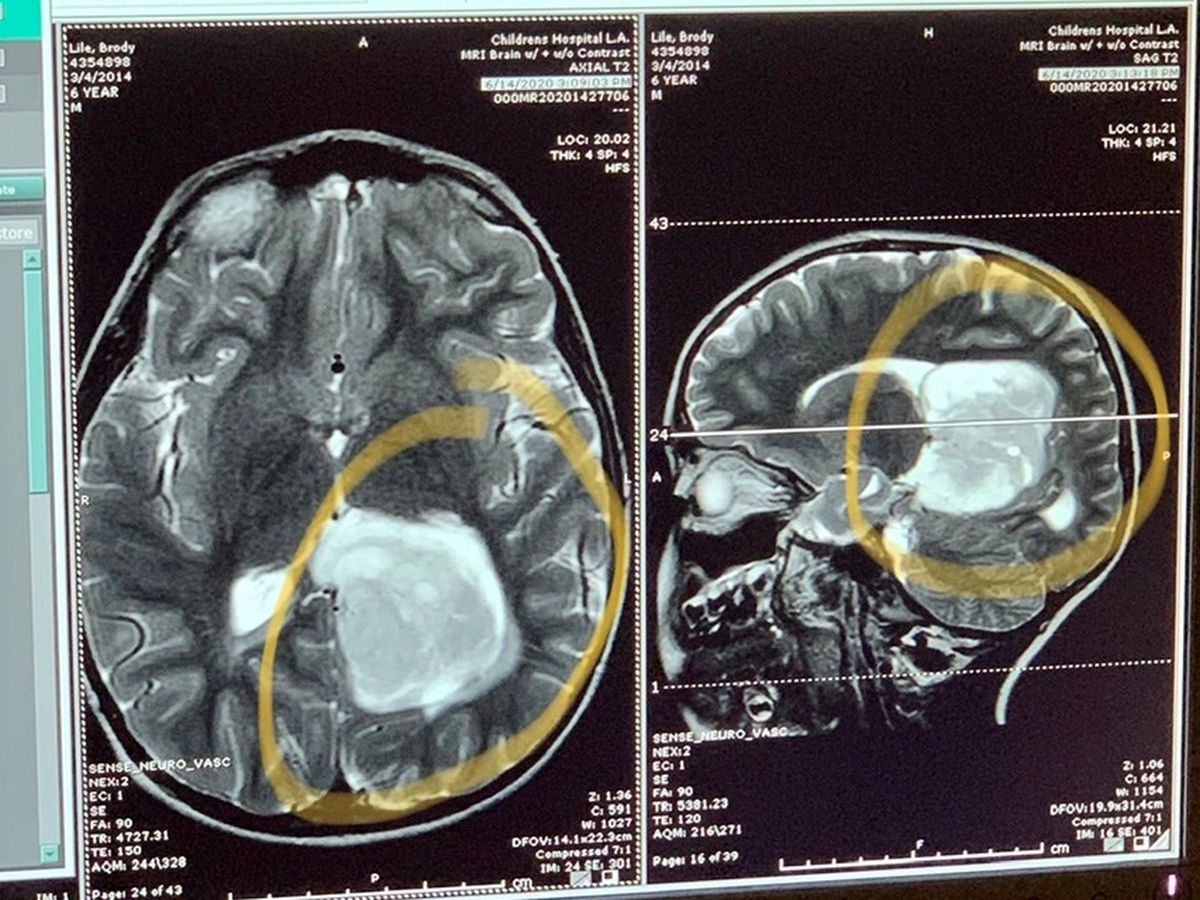

We (Tim and Renee-Grandma and Grandpa) found out on Saturday 6/13 our Grandson Brody who is 6 years old, was having seizures and was rushed to the Emergency room. A Cat scan revealed an egg sized mass in his brain. He was transferred to Children’s Hospital LA where they performed an MRI to discern its Actual location. Brody underwent 6 hours of Brain surgery and it seems to have been a successful one!!! Now the recovery begins and the hopes are “High” there will be no deficits as Brain surgery is a delicate process. All this is going on while his parents are closing on a home sale this Friday 6/19. They scraped together all they had for a down payment and closing costs. Brody’s family is doing everything they can to support during this stressful time. We are asking for any support to help This young family with Brody’s medical bills that are mounting up!!! We appreciate all the prayers and support thus far!!!

We (Tim and Renee-Grandma and Grandpa) found out on Saturday 6/13 our Grandson Brody who is 6 years old, was having seizures and was rushed to the Emergency room. A Cat scan revealed an egg sized mass in his brain. He was transferred to Children’s Hospital LA where they performed an MRI to discern its Actual location. Brody underwent 6 hours of Brain surgery and it seems to have been a successful one!!! Now the recovery begins and the hopes are “High” there will be no deficits as Brain surgery is a delicate process. All this is going on while his parents are closing on a home sale this Friday 6/19. They scraped together all they had for a down payment and closing costs. Brody’s family is doing everything they can to support during this stressful time. We are asking for any support to help This young family with Brody’s medical bills that are mounting up!!! We appreciate all the prayers and support thus far!!!

We (Tim and Renee-Grandma and Grandpa) found out on Saturday 6/13 our Grandson Brody who is 6 years old, was having seizures and was rushed to the Emergency room. A Cat scan revealed an egg sized mass in his brain. He was transferred to Children’s Hospital LA where they performed an MRI to discern its Actual location. Brody underwent 6 hours of Brain surgery and it seems to have been a successful one!!! Now the recovery begins and the hopes are “High” there will be no deficits as Brain surgery is a delicate process. All this is going on while his parents are closing on a home sale this Friday 6/19. They scraped together all they had for a down payment and closing costs. Brody’s family is doing everything they can to support during this stressful time. We are asking for any support to help This young family with Brody’s medical bills that are mounting up!!! We appreciate all the prayers and support thus far!!!